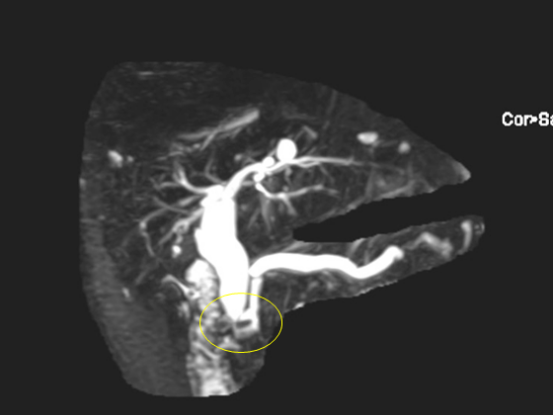

磁共振下见到的扩张的胆管

在做好充分的术前准备后,经过与患者及家属沟通,我院超声科团队在局麻下为患者行超声引导下行经皮经肝胆管穿刺置管引流术(PTCD)。在B超精准定位下经皮肝胆管穿刺成功,置管后引出胆汁,术后患者无明显不适,安返至病房进一步治疗和观察;次日李大爷黄疸、肝功能等情况逐渐得到缓解,精神状态明显好转,患者及家属对该手术治疗也感到很欣慰。